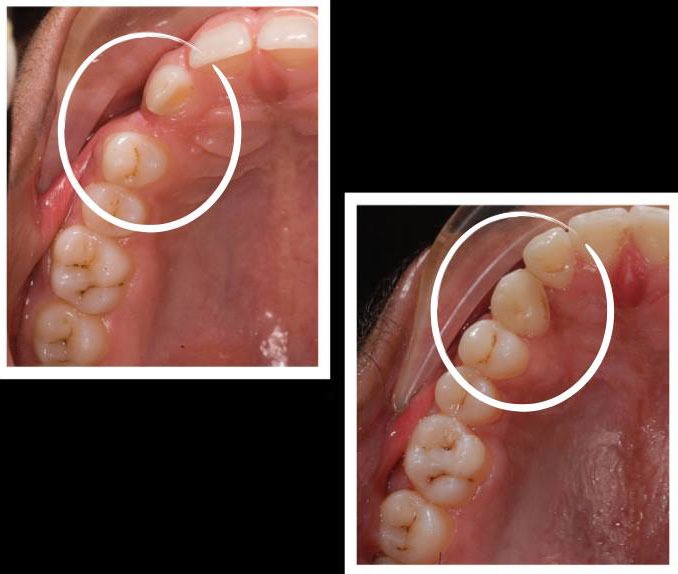

An orthodontist can help, to get the canine back into its rightful position |

To get a beautiful balanced smile!!! |

Nothing’s impossible in orthodontics… |